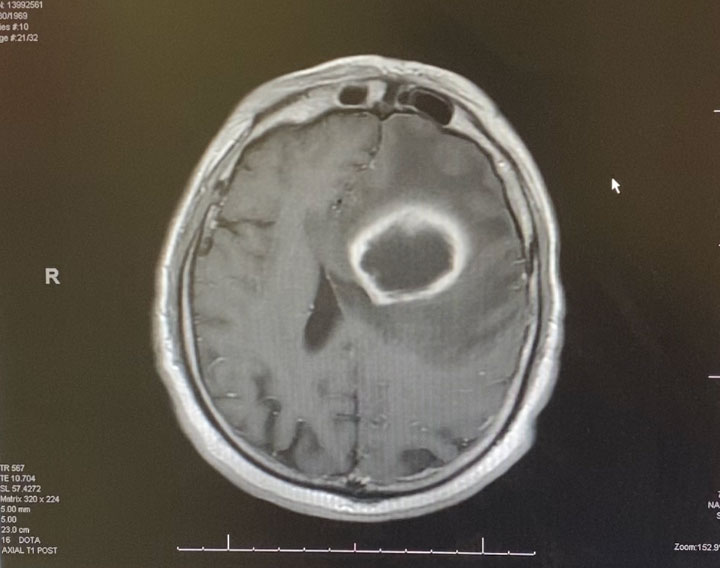

Postoperatively, the patient was started on broad spectrum IV antibiotics, under the supervision of an Infectious Disease consult. Clinically, the patient gradually recovered. Within weeks, the patient had fully recovered and was neurologically intact. Gram stains were suspicious for the presence of bacteria (encapsulated cocci). Cultures never grew out any organisms. The patient was treated with several weeks of broad spectrum IV antibiotics. The patient made a full recovery. (Image 3, axial post contrast MRI from 3 months post-op shows resolution of brain abscess and surrounding edema. )

Image 3: Axial post contrast MRI from 3 months post-op shows resolution of brain abscess and surrounding edema.